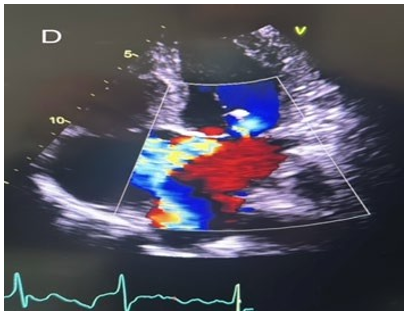

Tricuspid valve repair was done using MC-III ring downsize annuloplasty for functional TR. There was no intra-operative complications and aortic cross clamp time was 99 minutes and cardiopulmonary bypass time was 136 minutes. TEE post procedure showed well-functioning mitral valve prosthesis with no para valvular leak and mild tricuspid regurgitation. Post-operatively, patient was extubated 18 hours post-operatively and required small doses of inotropic support until day 2. She was transferred to the ward on day 3 and had uneventful post-operative course. She was discharged home with therapeutic level of warfarin at day 11 post-operatively. Pre-discharge echocardiography showed well –functioning mitral valve prosthesis with mean gradient of 2 mmHg (Figure 1 D). Tricuspid valve repair was satisfactory with mild tricuspid regurgitation. Patient was seen 6 months post-operatively and remained well with no shortness of breath.

Figure 1D: Post-operative four chamber view of transthoracic echocardiography showing well-functioning bioprosthetic mitral valve.